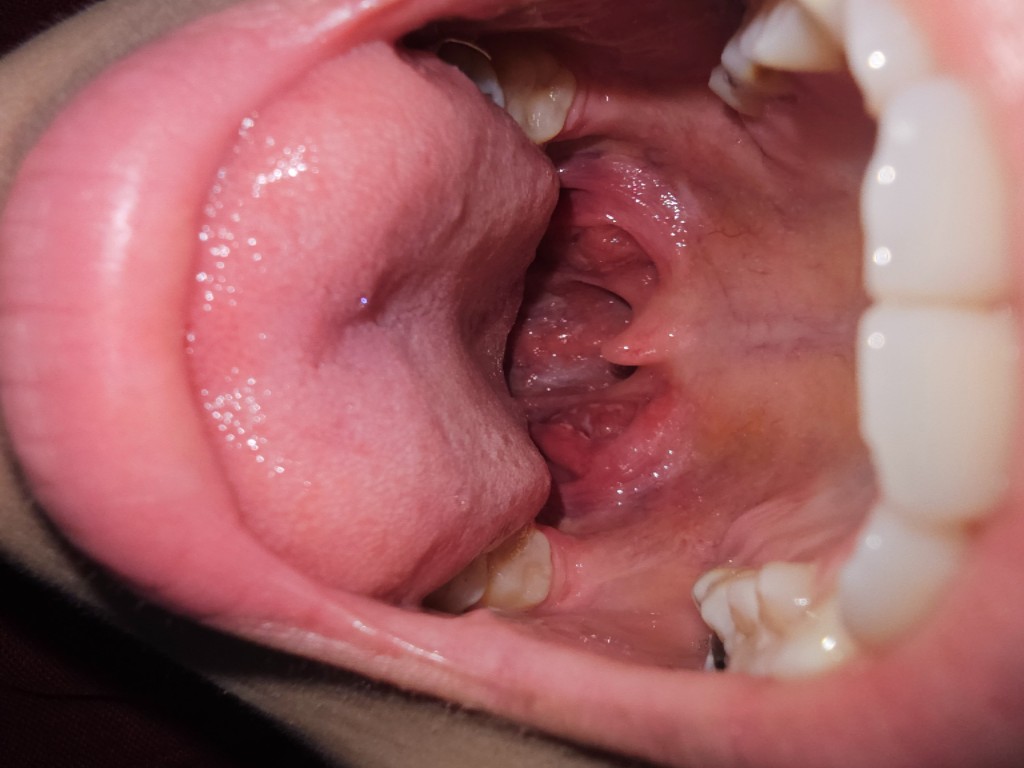

เจ็บคอบ่อยมาก มีแผลเปื่อยตรงให้ใกล้สิ้นไก่ ดูให้หน่อยว่าเป็นท่อมซินอักเสบไหม

เราเป็นแผลเปื่อยบริเวณนี้บ่อยมากแทบทุกเดือน ไปหาหมอหมอก็บอกว่า คออักเสบ ร้อนใน ให้ยาอม็อกซี่มากิน เราอยากรู้ว่า เราควรจะทำยังไงไม่ให้เป็นอีก เบื่อมาก แล้วเราก็มีนิ้วท่อมซินด้วย อยู่ลึกมองไม่เห็นแต่รู้สึกว่ามี